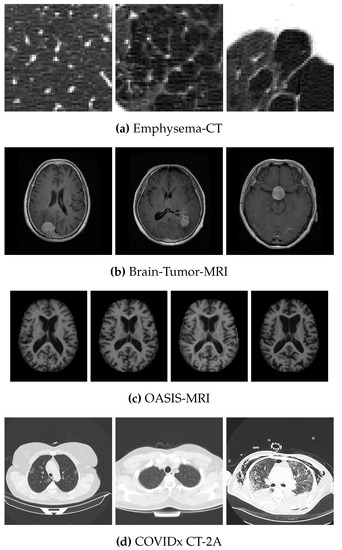

4.1. Data Sets

- Cheng, J.; Huang, W.; Cao, S.; Yang, R.; Yang, W.; Yun, Z.; Wang, Z.; Feng, Q. Enhanced Performance of Brain Tumor Classification via Tumor Region Augmentation and Partition. PLoS ONE 2015, 10, e0140381. [Google Scholar] [CrossRef]

- Marcus, D.S.; Wang, T.H.; Parker, J.; Csernansky, J.G.; Morris, J.C.; Buckner, R.L. Open Access Series of Imaging Studies (OASIS): Cross-sectional MRI Data in Young, Middle Aged, Nondemented, and Demented Older Adults. J. Cogn. Neurosci. 2007, 19, 1498–1507. [Google Scholar] [CrossRef]

| Data Set | No. of Images | Size | Classes | No. of Images per Class |

| Brain-Tumor-MRI | 870 | 3 | 143–436–291 | |

| OASIS-MRI | 436 | 4 | 336–70–28–2 | |